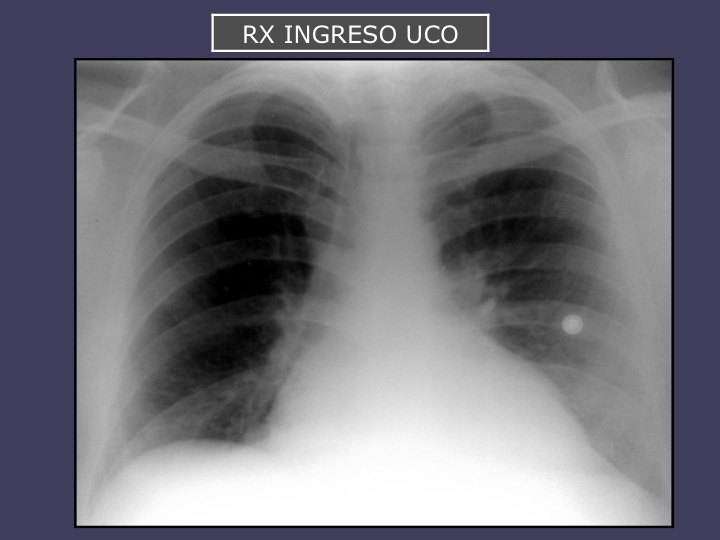

Este miércoles el Dr. Alberto Cozzarin presentará un ateneo clínico de un paciente con IAM y fumador de PACO.